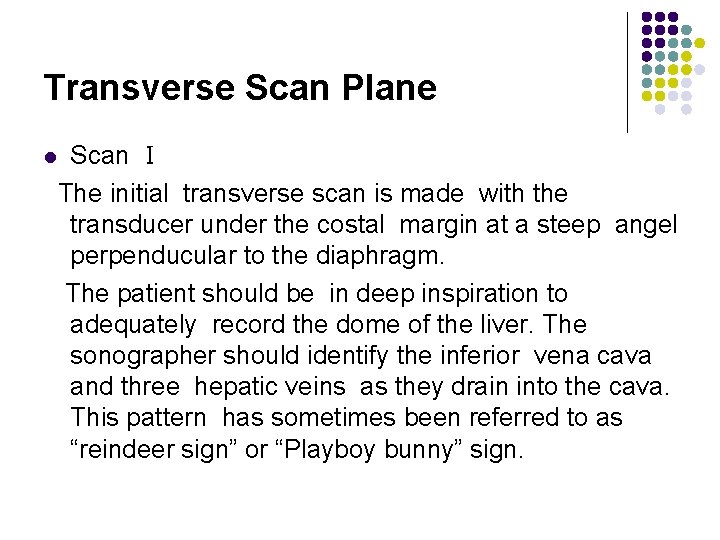

Transverse Scan Plane l Scan Ⅰ The initial transverse scan is made with the transducer under the costal margin at a steep angel perpenducular to the diaphragm. The patient should be in deep inspiration to adequately record the dome of the liver. The sonographer should identify the inferior vena cava and three hepatic veins as they drain into the cava. This pattern has sometimes been referred to as “reindeer sign” or “Playboy bunny” sign.

l The sonographer should identify the inferior vena cava and three hepatic veins as they drain into the cava. This pattern has sometimes been referred to as “reindeer sign” or “Playboy bunny” sign.